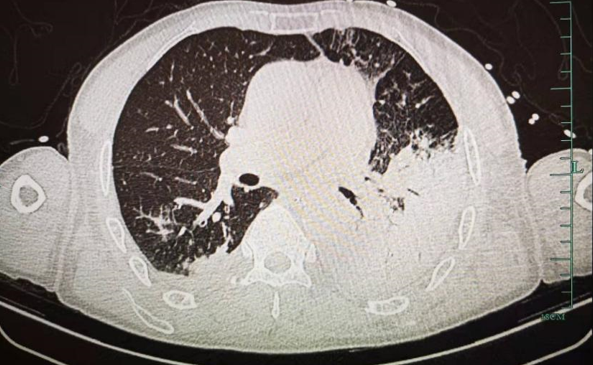

图片可见一侧肺部几乎变成了“白肺”,存在严重炎症

急忙被送到浙大四院,抽血、胸部CT后,查出严重的肺炎。最后通过肺泡灌洗液宏基因测序,明确是“鹦鹉热衣原体”细菌感染。